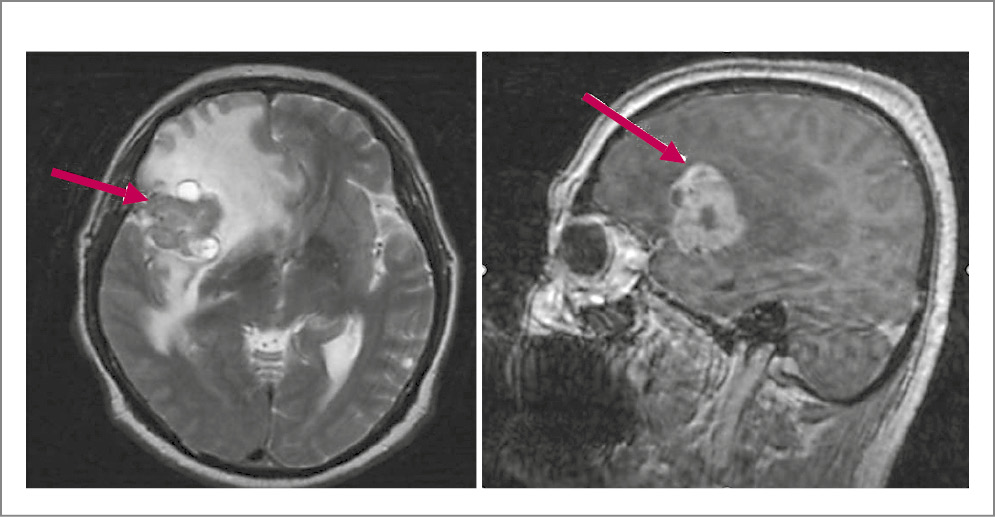

По данным магнитно-резонансной томографии (МРТ) ГМ с контрастированием в островковой доле справа с распространением на лобную и височную визуализируется внутримозговое кистозно-солидное образование с бугристым контуром размером 3,7×3,3×2,9 см. Отмечаются выраженный перифокальный отек с переходом на лобную и височную доли, базальные ядра со смещением срединных структур на 1,3 см. Аналогичные образования выявлены в задних отделах левой височной доли и левом полушарии мозжечка, размеры которых составили 1,1×0,8 и 0,5×0,6 см соответственно. В гипофизе определяется кровоизлияние. Соответственно, у больного имеются объемные образования в правой островковой, левой височной долях и левом полушарии мозжечка с кровоизлиянием в гипофиз (рис. 1, 2).

Рис. 1. Пациент Л., 66 лет. МРТ ГМ. Крупное кистозно-солидное образование вторичного характера в правой островковой доле размером 3,7×3,3×2,9 см, с выраженным перифокальным отеком, приводящим к смещению срединных структур влево (стрелки).

Рис. 2. Больной Л., 66 лет. МРТ ГМ: a, b – кистозно-солидное образование вторичного характера в левой височной доле размером 1,1×0,8 см с выраженным накоплением контраста солидным компонентом; c – контрастпозитивное образование вторичного характера в левой гемисфере мозжечка размером 0,5×0,6 см, которое не определяется на нативных программах (стрелки).